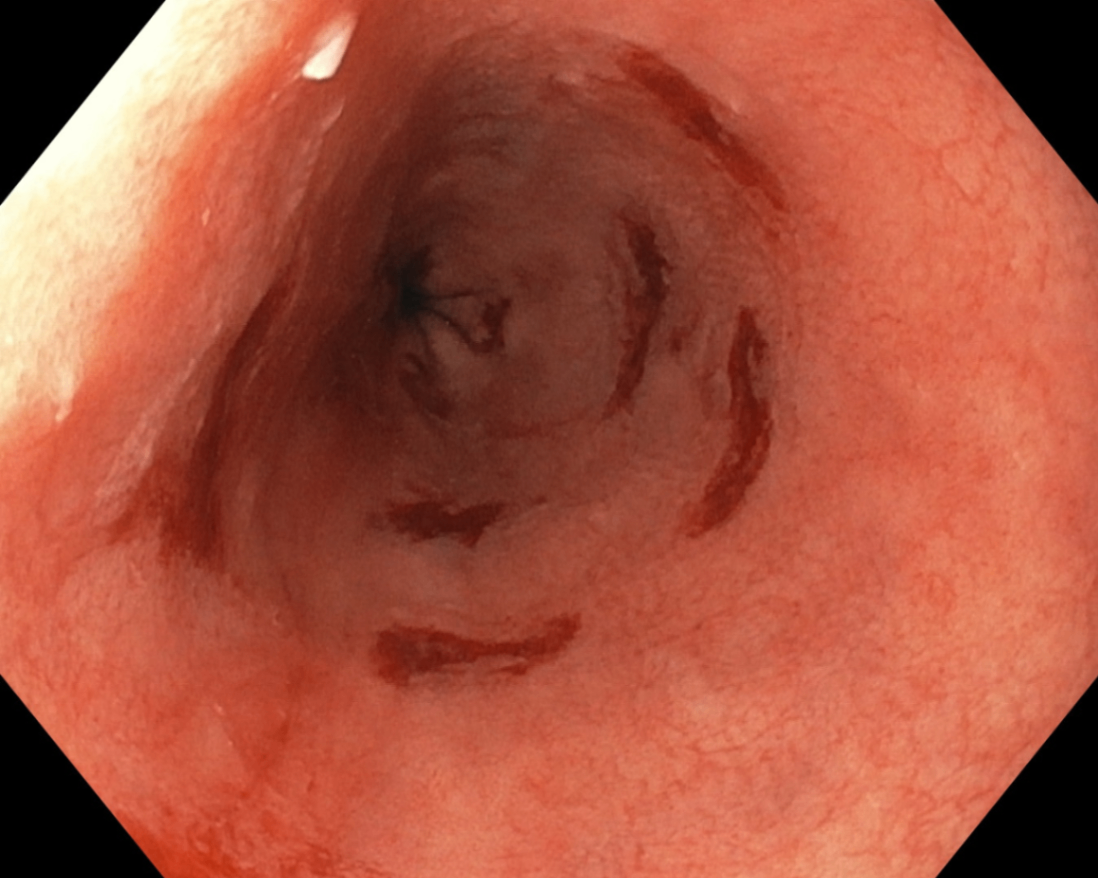

2) 육안 소견

위식도 이행부(gastroesophageal junction)에 창백하고 평평한 정상 편평상피와 대조되는 붉고 거친 점막이 관찰됨

Seattle Protocol Biopsies, Wikimedia Commons